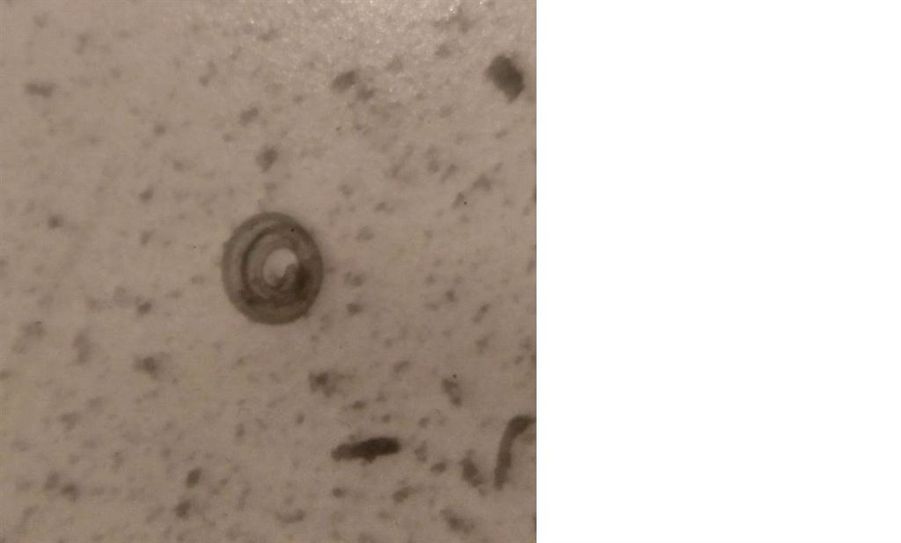

Landkreis (eb). Bei der routinemäßigen Untersuchung einer Wildschweinprobe aus dem Raum Scheeßel / Fintel wurde Ende Mai erstmalig im Landkreis der Parasit „Trichinella pseudospiralis“ im Fleisch nachgewiesen. Auch der Mensch kann sich mit Trichinellen infizieren.

Trichinellen sind Fadenwürmer, die zum Beispiel im Fleisch von Wildschweinen vorkommen und beim Menschen zu milden bis schweren Erkrankungen (Durchfall, Fieber, Muskelschmerzen, Herzmuskelentzündungen) führen können.

Aus diesem Grunde werden alle Wildschweine und Hausschweine durch den Landkreis routinemäßig auf Trichinellen untersucht. Die mikroskopisch kleinen Parasiten lassen sich mit einer speziellen Analyse (Disgestionsmethode) nachweisen. Das Ergebnis der positiven Probe wurde durch das nationale Referenzlabor des Bundesinstitutes für Risikobewertung (BfR) bestätigt und ein sehr hoher Gehalt der Spezies „Trichinella pseudospiralis“ ermittelt.